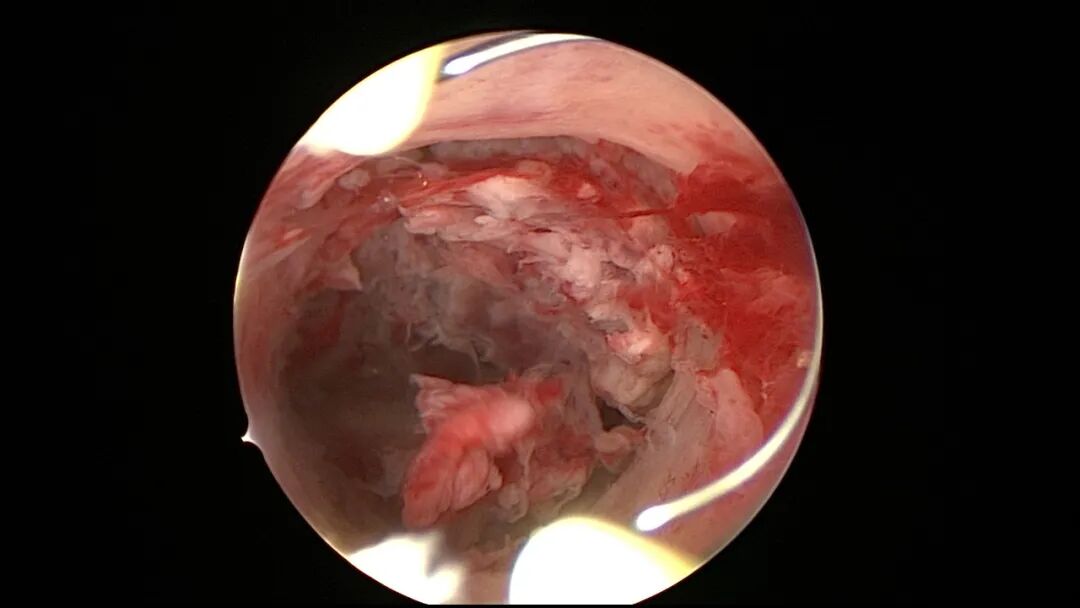

第五次宫腔镜:2023年8月初自然妊娠,药流不全,2023年8月底行宫腔镜清除残留胚物。宫腔下段前壁及左侧壁胚物残留,胚物与宫壁粘连,双侧输卵管开口可见,内膜稍苍白。单极电切环切除残留胚物组织,恢复宫腔形态,宫腔注入防粘剂,未放置球囊,患者拒绝送病检。